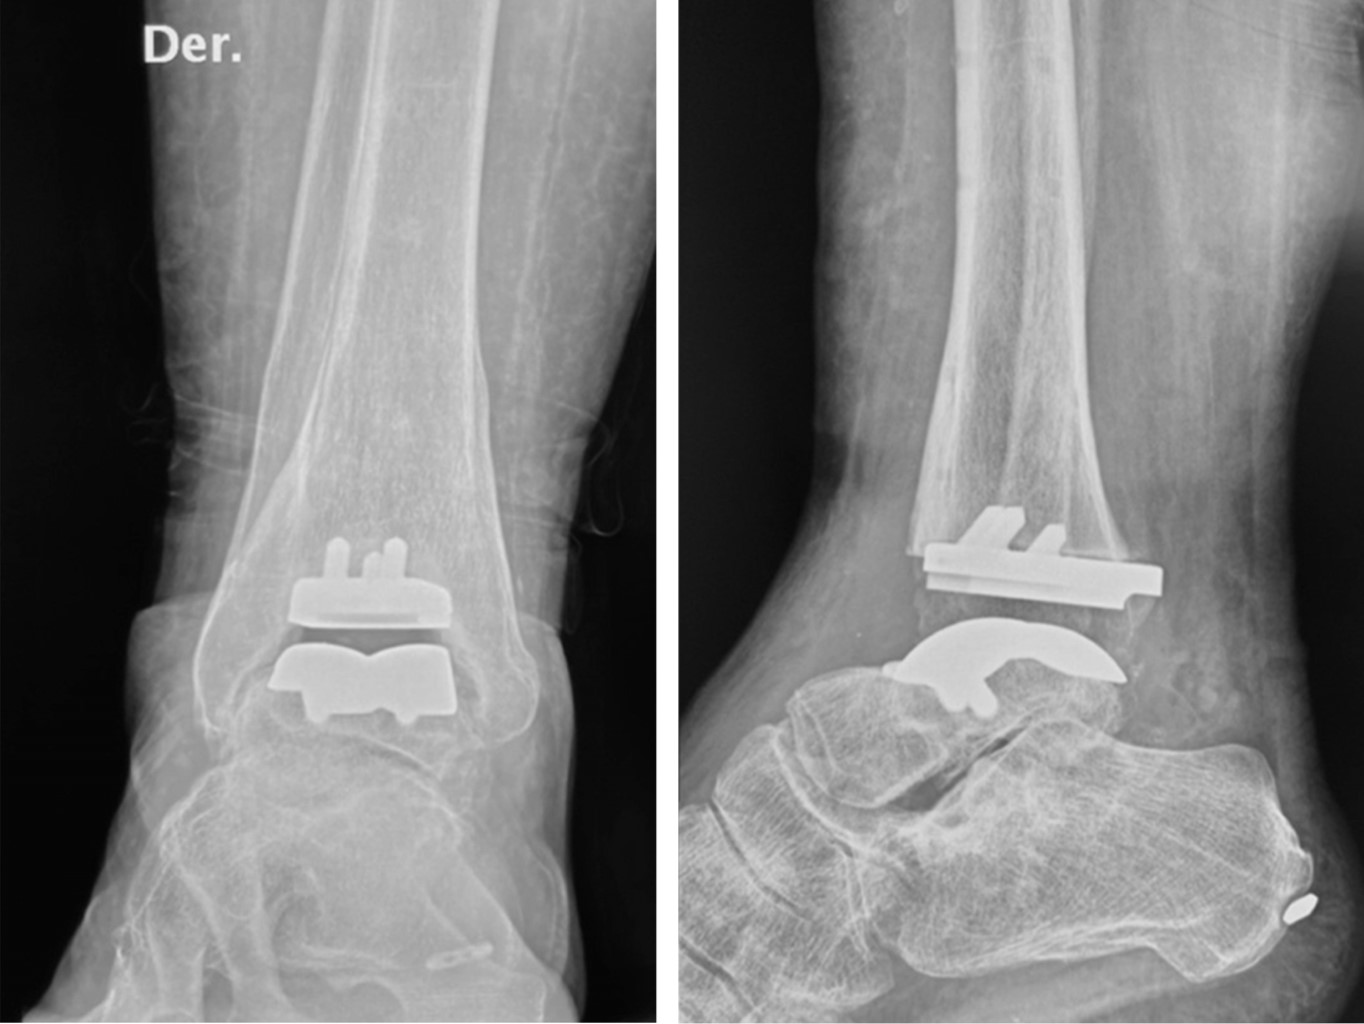

Paciente masculino de 61 años de edad con dos cirugías previas en el tobillo derecho. La primera fue una artroscopia de tobillo para limpieza articular con microfracturas por una lesión osteocondral medial y un año después una artrodesis tibio-astragalina con dos tornillos. Un año posterior a la artrodesis, y pese a que su evolución había sido satisfactoria en cuanto al dolor los primeros 12 meses, el paciente inicia con dolor medial progresivo con caminatas de larga distancia. Clínicamente no había arco de movilidad del tobillo y dolor moderado a severo a la palpación de la superficie medial a nivel del receso. Se le propone desmantelar la artrodesis y colocar una prótesis total de tobillo derecho.

Radiográficamente se observa consolidación parcial de la artrodesis de tobillo con una adecuada alineación sin datos de aflojamiento de los tornillos (Figura 4).

Bajo sedación y bloqueo poplíteo por ultrasonido con torniquete en muslo, se realiza abordaje anterior de tobillo de 8 cm entre el tendón tibial anterior y el extensor largo del hallux. Se hace el retiro de dos tornillos canulados de 6.5 mm y se observa que en el receso medial no había consolidación, sino una franca pseudoartrosis, mientras que en la zona anterior sí había consolidación. Se preparó la articulación con cinceles tratando de conservar la arquitectura de la mortaja. Una vez móvil el tobillo, se lleva a cabo la técnica quirúrgica como está descrita.

El paciente estuvo sin apoyo durante tres semanas y posteriormente marcha con muletas por una semana más. Hoy en día, a 20 meses de la cirugía, el paciente se encuentra con dorsiflexón de 20o y flexión plantar de 25o; asimismo, puede caminar de forma recreativa, completamente satisfecho de haberse hecho la cirugía de prótesis total (Figura 5).

Figura 4

Figura 5